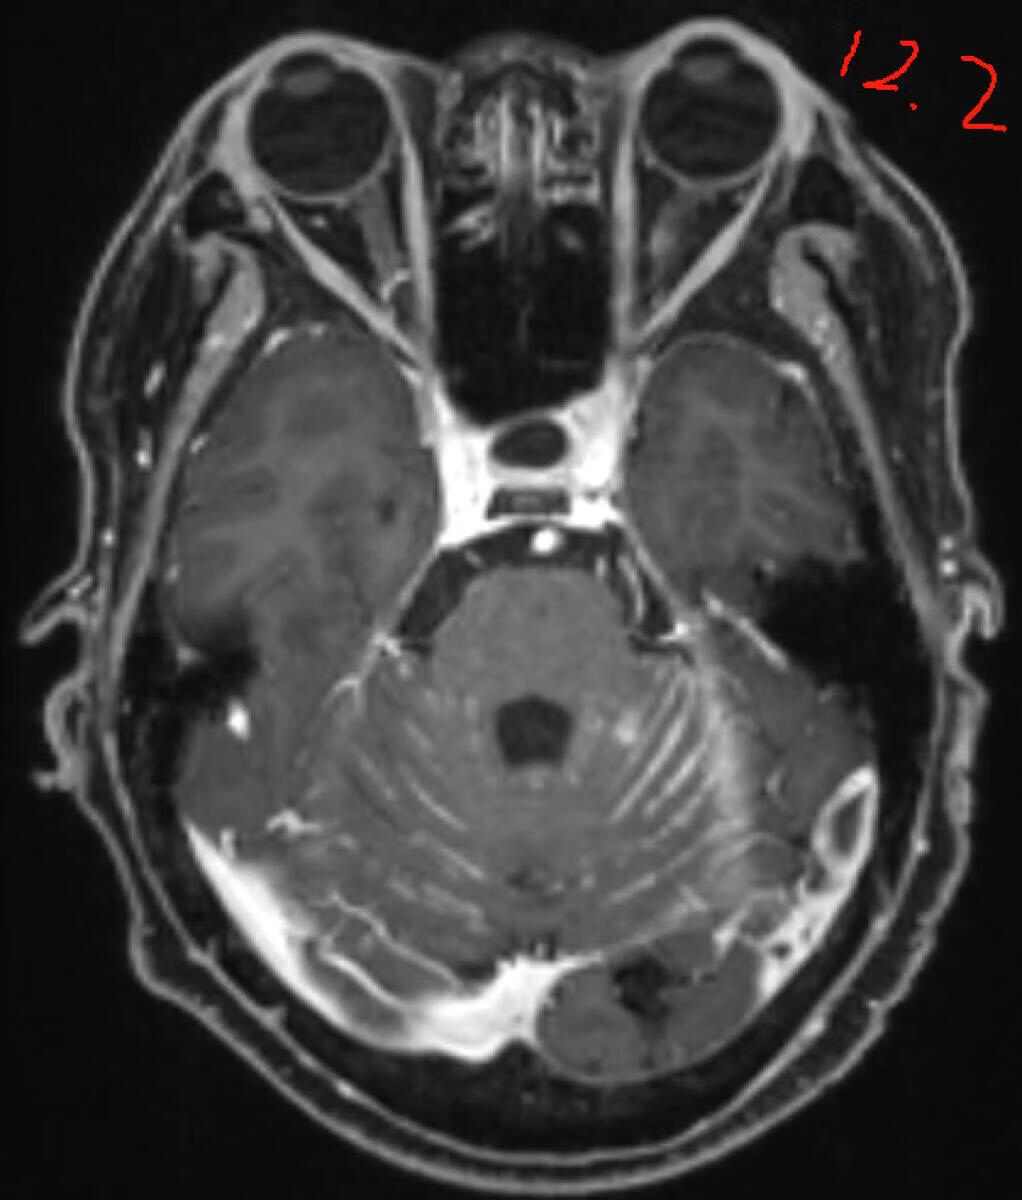

肺腺伴脑转移,放化疗后一直单线奥西,12月初复查头颅新增病灶较前增大,考虑有脑膜转移,目前偶尔头晕,头痛,持续时间短(自确诊以来偶尔都有),本地医生建议双倍奥西,现已经口服双倍20多天,请问没有症状的脑膜转移需要鞘注吗?脑膜转移可逆吗?有没有可能双倍奥西后脑膜转移就消失,病灶缩小了?求各位大佬指导